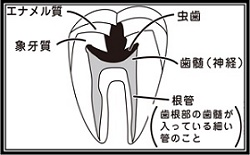

⑤ 次に、仮詰めをします。 虫歯が神経まで達して炎症を起こしているので、人によってはズキズキとした痛みを感じる方もいます(>_<)

虫歯が神経まで達して炎症を起こしているので、人によってはズキズキとした痛みを感じる方もいます(>_<)